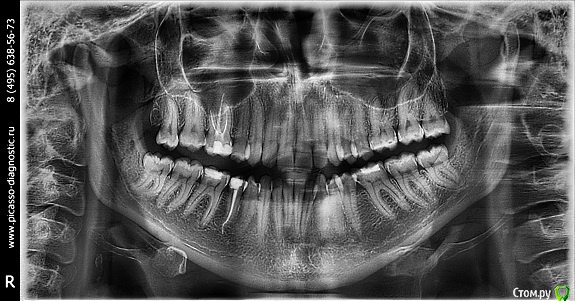

zimazima Опубликовано 20 ноября, 2015 Поделиться Опубликовано 20 ноября, 2015 Добрый вечер!Опытные ортодонты, скажите, пожалуйста, будет ли необходимо в моем случае удалять нижние 4ки? Какова вероятность того что НЧ выйдет вперед после ношения брекетов? предыстория: в 17 лет носила брекеты на ВЧ, т.к. слева клык рос поверх ряда удалили 4ку и поставили на ее место клык...при этом ВЧ потеряла симметрию((и кажется что проявилось это спустя годы (сейчас мне 30). и теперь за счет того что НЧ не ровнялась зубы начали разворачиваться опять... вопросы:- какова вероятность того что удаление нижних 4к не потребуется при лечении?(ортодонт говорит что можно поносить пол года и посмотреть в процессе, имеет ли это смысл? или лучше не терять время, может все очевидно?...)- можно ли оставлять 8ки?- реально ли вернуть центр ВЧ на место если удалить 4ку слева?- при удалении нижних и верхних 4к как сильно сузится лицо и подбородок станет ли еще более выпирающим? (лицо у меня и без того узкое и длинное, достаточно большой нос картошкой и выступающий подбородок) не станет ли хуже?- не будет ли после лечения других проблем с искривлением лица (оно у меня сейчас не симметричное - глаза на разном уровне))), на фото вижу особенно это(( в общем в жизни не так вроде бы все и плохо выглядит - на фото просто кошмар - сама посмотрела и уже готова на все.волнуюсь не будет ли хуже в моем случае? очень благодарна за любые ответы - советы - комментарии! спасибо!выложу доп фото по запросу любые нужныеЗлобина А.В. Заключение.pdf Ссылка на комментарий

m.d.n Опубликовано 21 ноября, 2015 Поделиться Опубликовано 21 ноября, 2015 эммм ну можно тут по разному работать. внизу кроме 8 ничего неудалял бы вообще. если побыстрее то слева 4. если не торопитесь то все 8 удалить открыть место под удаленный премоляр вернуть центры и имплант вместо ранее удаленного .как то так Ссылка на комментарий